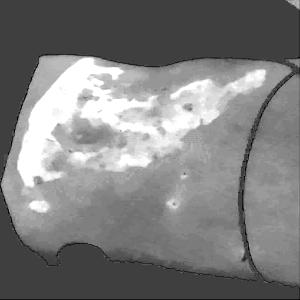

Figure 2a. illustrates the information retrieved from this CNN model from various layers of the architecture that is used to create a BAM map, which is used to segment the burn injury from normal skin in a 2D image. First, the heatmaps for the activations of the first convolutional layer are computed (Figure 2a(ii)), and then Grad-CAM heatmap is computed using the last convolutional layer (Figure 2a(iii)). Once the first convolutional layer heatmaps and Grad-CAM are generated, the algorithm uses a three-round iterative process to select activation heatmaps that have the highest correlation to the Grad-CAM heatmap among the channels of the first layer activations. After the process of correlating and selecting heatmaps is completed (Figure 3 ), segmentation masks are created next (Figure 4). A final composite BAM mask is created as illustrated in 2b(i). Finally, figure 2b (ii-iii) illustrates how the BAM mask is superimposed on the input image to segment the burn injury area, and how edge detection may be applied to the BAM mask in order to obtain a fine-tuned segmented boundary superimposed on the input image.

Figure 5 shows several burn image examples of patients with different sized burns in different body locations, for which the Grad-CAM heatmap, BAM heatmap, BAM masks, and final superimposed images were created. These results allow us to understand the clinical accuracy of burn segmentation from 2D images using BAM. These images show various degrees of burn. It is evident from the results that given skin burn images and the corresponding Grad-CAM heatmaps highlighting the burn regions even partially, the BAM heatmap is able to highlight the burn regions and display a high resolution heatmap accurately. This is the main contribution of BAM. It can be seen from the figure that the BAM heatmaps display different contrast levels in highlighting the burn regions. More precisely, the more superficial burns are highlighted with a lower contrast to the normal skin. The deeper burns, on the other hand, are highlighted with a higher contrast to the normal skin. Nevertheless, the contrast between the burn regions and the normal skin in the BAM heatmaps is sufficient for generating the binary segmentation masks even for the more superficial burns. As evidenced, the BAM heatmaps can successfully be converted into accurate binary segmentation masks. The rightmost column of the figure shows the BAM segmentation masks on top of the input images in order to better visualize the effectiveness of BAM in segmenting the burn regions. In short, comparing the Grad-CAM heatmaps against the BAM heatmaps and BAM segmentation masks provides evidence for a significant improvement in generating heatmaps that are both class-discriminative and fine-grained.